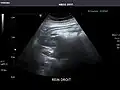

Kidneys: Right and left kidneys measure 11.5 cm and 12 cm in length respectively. No hydronephrosis. Small left lower pole kidney cyst.

Right kidney -